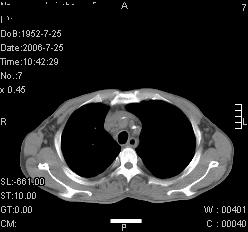

患者,男,54岁,咳嗦,咳痰20天。抗炎治疗2周。现esr76mm/h,目前患者症状明显好转,但发现两次ct片未见明显变化。两次分别做与7.25、7.31。第一次诊断右肺上叶炎症累计胸膜。大家看,从影像上内排除结核吗?

结核的可能性非常大,右上肺病变应该考虑干酪性肺炎。理由:

1.纵隔内多发淋巴结肿大。

2.esr76mm/h。

3.虽经抗炎治疗肺窗病灶有所吸收、减小,但纵隔窗病灶形态、密度、范围无明显变化。如果是单纯的大叶性肺炎,“抗炎治疗2周,目前患者症状明显好转”病灶应该基本消散了,至少也处于吸收消散期,密度变淡、范围变小。同时本病例所示其内的密度不均匀,见多发大小不一空洞样影也不符合大叶性肺炎吸收消散期表现。

病灶特点:片状 索条 结节混杂影,部分融合,密度不均,广泛累及相应胸膜.

临床治疗;二周未吸收.但症状好转.

多考虑:肺结核.